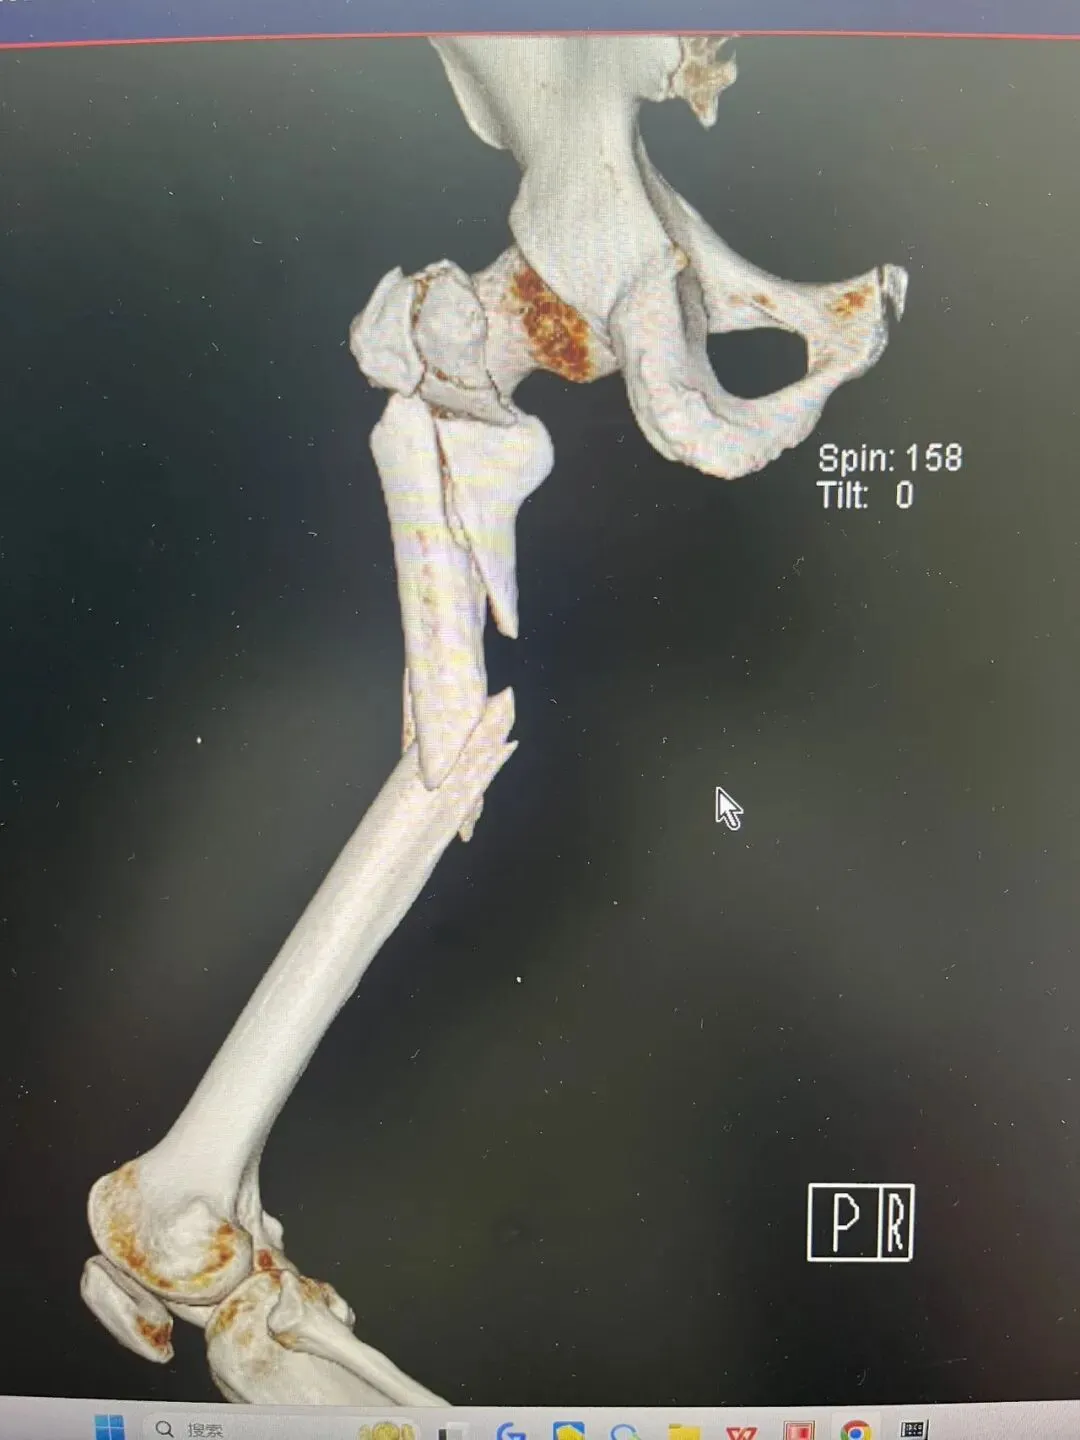

再看看在门诊看到的外院一例相似患者,

为了复位骨折而复位骨折的切开做,当然切开没有绝对的错,早期没有髓内钉的时候,我们也切开做,但这样的切开,就没有创伤骨科理念。

术后2月,远端锁钉都退了。